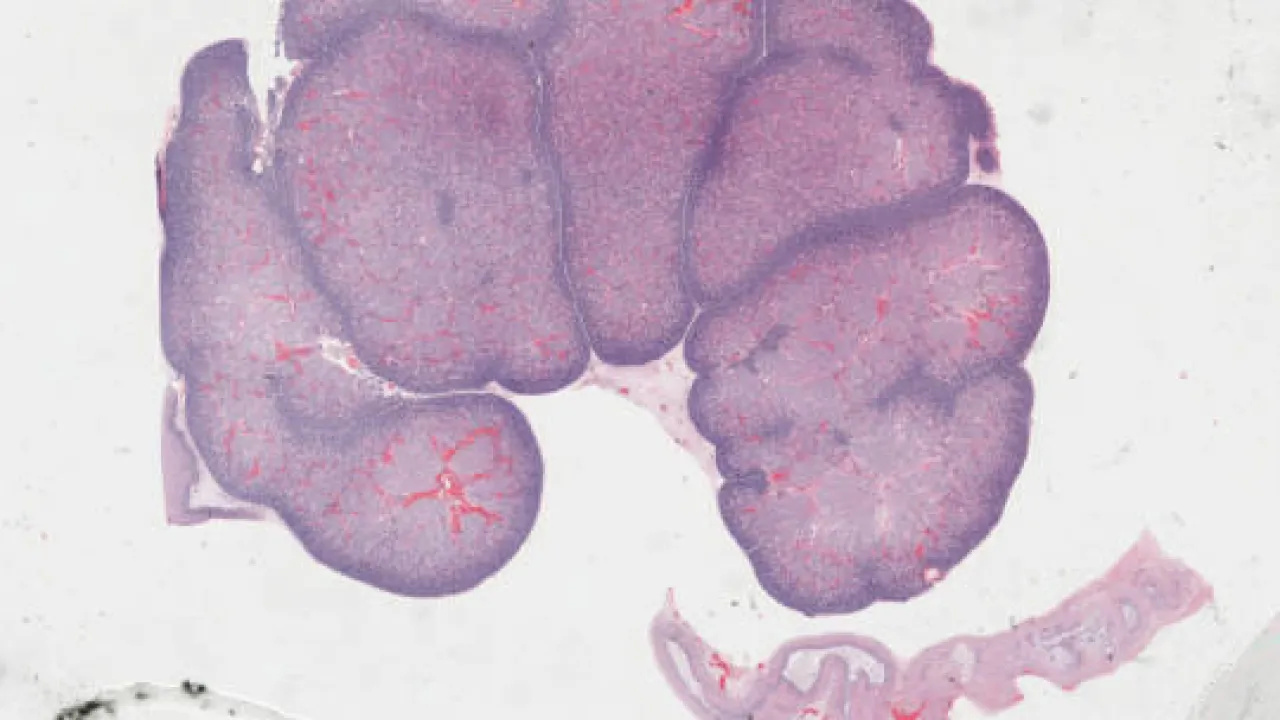

Kidney, Metanephric adenoma